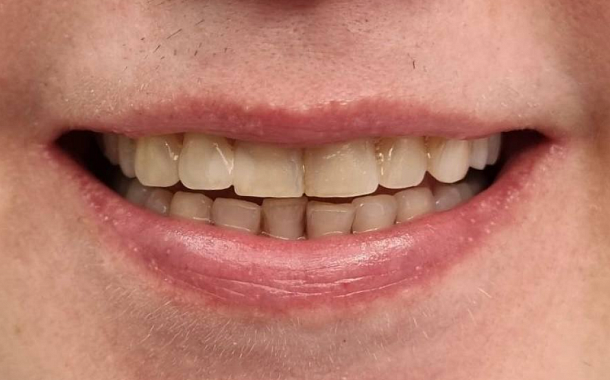

- Визуализация результатов: Пациенты могут увидеть предполагаемый результат лечения еще до его начала, что помогает в принятии информированных решений.

- Минимизация погрешностей: Высокая точность сканирования снижает риск ошибок при изготовлении протезов и реставраций.